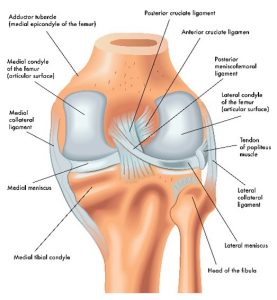

All of the major joints are complicated with many ligaments and other structures, each having an important function.

The knee joint is straightforward.

The lateral (outside of knee joint) and medial (inside of knee joint) meniscus cushion the femur (thigh) bone and tibia (shin bone) so your knee can bend and straighten without wearing down the bone.

Ligaments that surround the knee joint hold the bones together and form a tight, secure joint.

It turned out that I not only severed my left medial meniscus, I also tore my anterior cruciate ligament (ACL), The ACL holds your bones together from front to back. When this tore, I felt like whenever stepped down my upper leg still kept going forward. It was a scary feeling, I felt like my leg was going to come apart at my knee. Yikes!